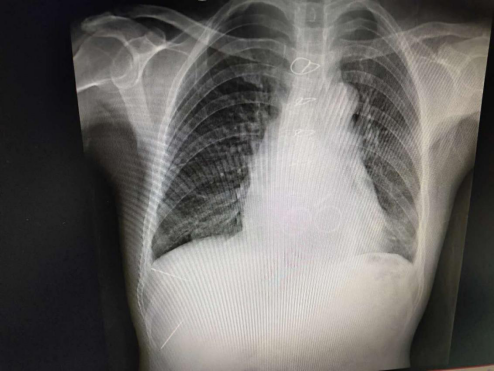

家住广元市朝天区临溪乡淖池村5组的张某某,长期饱受病痛折磨,日常自理诸多艰难,更无生活质量可言。十年前经检查提示“风湿性心脏瓣膜病,联合瓣膜病变”。2008年,在市第一人民医院心胸外科行二尖瓣、主动脉瓣机械瓣置换术。术后患者严格听从医生指导,身体恢复至能正常生活。

可是近一年来,患者反复出现腹胀、心悸等症状,带着不安再次回到市第一人民医院检查,未曾料想的是心脏彩超提示“三尖瓣中-大量反流”,手术指征明确。但是患者体质差,系心脏瓣膜二次手术,风险大,难度高,术中大出血几率高,术后低心排综合征、心功能衰竭等严重并发症出现的可能性大,死亡率高。经北京常春藤高端医学联盟心脏外科项目李巅远教授团队与市第一人民医院心胸外科张文林主任、张熠副主任医师及团队医生反复商榷,认为此例手术虽然难度大、风险高,但是为了能让患者活下去必须手术。确定后,专家们齐心聚智为患者制定了手术方案,力争把风险降至最低。一切准备就绪,2018年12月30日,患者在体外循环下行三尖瓣机械瓣置换术,手术历时3小时45分,顺利术毕。患者于术后第2天就由重症监护室转入专科病房治疗。目前病情平稳,生命体征正常。

心脏瓣膜病三瓣(主动脉瓣、二尖瓣、三尖瓣)机械瓣置换手术,同时系10年后的二次手术,手术难度大,风险高,死亡率高。手术的成功实施填补了广元此类技术的空白,开创了广元医疗技术的先河,是市第一人民医院心胸外科医疗技术水平已达国内先进水平的又一例证!市第一人民医院心胸外科团队将一如既往、不辱使命、磨砥刻厉造福广元及川陕甘毗邻地区的患者!